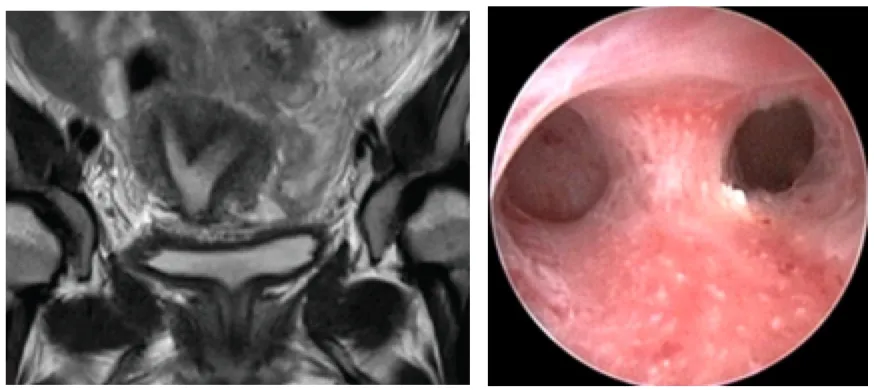

30세 여성이 반복적으로 3회 유산을 경험하였다. 환자는 임신을 유지하는 데 어려움을 겪고 있으며, 이에 대한 원인을 찾기 위해 병원을 방문하였다. 골반 MRI 및 자궁경 검사 결과이다. 가장 적합한 진단은 무엇인가?

자궁강 내 중격이 관찰되며 fundus가 둥그런 모습을 보여 중격자궁으로 진단한다.

• 반복 유산을 주소로 내원한 환자의 MRI, 자궁경 검사 상 자궁 부속기의 기형이 관찰된다.

• 골반 MRI와 자궁경에서 중격이 관찰된다.

• MRI에서 fundus가 둥글게 나타나는 소견과 종합하면 중격자궁으로 진단 가능하다.

• Uterine didelphys(중복자궁): 자궁경 상 중격이 관찰되어 배제할 수 있다.

• Bicornuate uterus(쌍각자궁): MRI 상 fundus가 움푹 파인 형태로 나타나 감별 가능하다.